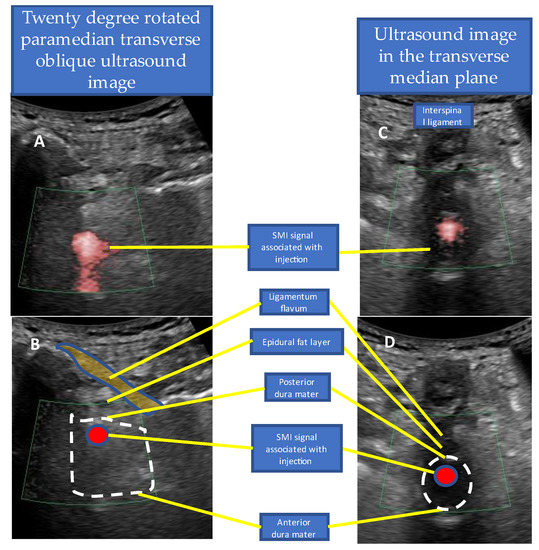

4.2. US-Guided Techniques

- Accurate needle tip guidance into the ligamentum flavum behind the epidural fat layer;

- Palpation of resistance by finger sense during ligamentum flavum insertion while confirming with sonography;

- Confirmation of the position of the needle tip in the ligamentum flavum;

- Tracing the spread of the drug in the epidural space using SMI during the injection.